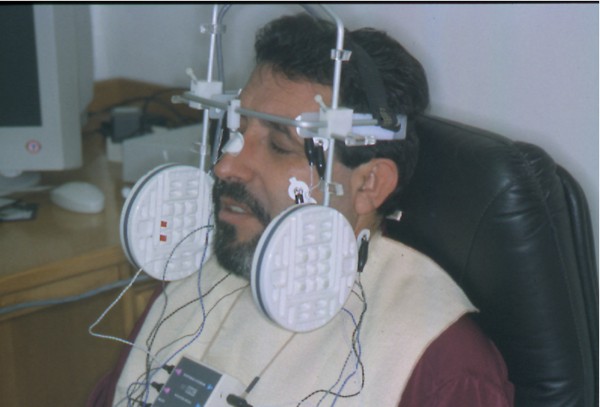

INTRODUCCIÓN El Bruxismo como entidad somática asociada al stress, responde a la mecánica de un Círculo Vicioso Patogénico, que Kawamura describiera hace ya muchos años. FACTOR DESENCADENANTE , que proveen las Interferencias a nivel dentario. En las entregas anteriores se desarrollaron las bases conceptuales de una OCLUSIÓN ORGÁNICA y los efectos de una mayor o menor Desoclusión según la variabilidad de los diferentes Factores Determinantes de la Oclusión. En síntesis; A-La obtención de una Oclusión en Relación Céntrica, nos permite devolver al sistema una elongación muscular fisiológica, sin acortamientos ni estiramientos musculares, sin las consecuentes estimulaciones de los husos neuro musculares, y; una situación estable de la A.T.M. con espacios articulares uniformes. B-El logro de una Guía Anterior que permita desocluir los sectores posteriores durante los movimientos excursivos, nos provée de una segunda y preponderante senda a transitar, que NO estimula por sus contactos excursivos la cincha Pterigo Maseterina, causante de las enormes destrucciones parafuncionales que es frecuente ver en bocas bruxómanas, y la axialización de las fuerzas sobre las piezas posteriores durante el cierre. C-Otorgando como consecuencia, Estabilidad a la tabla premolar-molar, simultaneidad en la recepción de fuerzas durante el cierre(A.T.M. y superficies oclusales). Obtendremos así una Oclusión estable y fisiológica, que no genere el FACTOR DESENCADENANTE del Bruxismo, siempre presente a nivel dentario. INTRODUCTION Bruxism as a somatic entity associated with stress responds to the mechanics of a Pathogenic Vicious Circle, described by Kawamura many years ago. Summarsing: A-Obtaining an oclusion in a Central Relation, allows us to return to the sistem a physiological muscular elongation, without muscular shotthenings or lenghthenings, without the following stimulations of the neuro-muscular huses and a stable situation of the Temporo Mandibular Joint with uniform articular spaces. B-The accomplishment of an Anterior Wide wich may allow disclusive the posterior sectors during the excursives movements, and the axial forces during the mandibular closure. C-Providing as a consecuence, axiality and stability to the posterior sections, responsible of the mandibular closure, through Sttopers, Equalitzers, A, B and C, to obtain a Oclusión Mutuamente Compartida: forces reception during mandibular closure (T.M.J. and Oclusal Surfaces) By this procedure, we should obtain a stable and physiological oclusion, that will not generate the chain link of factors that lead to Bruxism, always present at the dental level. MATERIALES Y MÉTODOS: La funciones articular y muscular, se analizaron mediante Bio Pack, en el pre, en el intra y en el post operatorio. Durante el diagnóstico, tratamiento y remontas, se utilizaron articuladores semi ajustables Wip Mix, totalmente ajustables Artex y arcos faciales correspondientes. El encerado de dianóstico se realizó, mediante la técnica de encerado progresivo de Peter K. Thomas. Los refuerzos a Perno Colado se llevaron a cabo con oro BIODENT YELLOW de ARGEDEN. Los tres juegos de provisionales utilizados, se hicieron con metacrilato termo curado. Las Restauraciones Periféricas Totales, fueron realizadas mediante porcelana CREATION de WILLY GUÉLLER, sobre oro BIODEN YELLOW de ARGEDEN. Los chequeos de los Contactos Interoclusales, se midieron con papeles de articular de 40 y 12 micrones, y mediante el analizador computarizado T-Scan. DESARROLLO Paciente varón de raza blanca, 42 años, complexión robusta y marcada hipertrofia maseterina. Fig.1 Fig.2 Fig.5 Se realiza un análisis pre-operatorio articular y muscular mediante Bio Pack, y oclusal mediante T-Scan, cuyos resultados muestran una evidente hiperactividad muscular en Temporal Anterior y Masetero Derechos, y contactos totalmente anómalos tanto en Oclusión Habitual como en Excéntricas. Fig. 6-7-8-9-10-11 Sensor de ruidos articulares Luego del primer intento de relajación mediante Laminillas de Long (Ref.6),Fig.12, registros y montaje, se observa la aparente presencia de una relación Borde a Borde, que luego se comprobaría que se trataba de una propulsión exagerada de su mandíbula en la búsqueda de contactos efectivos. Fig. 13-14 (Obsérvese el fenómeno de Patterson dado por la exclusiva guía de movimiento de la A.T.M. y la carencia de la Guía Anterior) Se procede a construir un JIG de LUCIA para lograr una desprogramación muscular adecuada, y se le indica permanecer con el colocado durante toda la noche anterior a la consulta, sin contactos dentarios posteriores. Aún en la duda, de que la obtenida sea una posición articular fisiológica, se procede a construir una Placa de Relajación sobre el último montaje obtenido, la que se ajusta cada dos días, y al cabo de tres semanas se procede a un tercer montaje obtenido de la nueva situación posicional. Fig.17-18 Se verifica entonces que estamos en realidad, ante una presunta CLASE II, después de tres métodos diferentes de relajación y transcurridos más de un més de múltiples sesiones para lograr una posición diagnóstica confiable a partir de donde comenzar a trabajar.(O.R.C.) Se adicionan entonces topes (montículos) en las caras oclusales de los primeros molares de la Placa de relajación, transformándola en una Férula Pivotante, de levísima altura, impidiendo el contacto de las demás piezas dentarias a fin de convertir la palanca en una de clase II (fisiológicamente el sistema se mueve según una palanca de clase III), y obtener de esa forma una descompresión de los espacios articulares, ya que si bien la A.T.M. era asintomática, estaba muy claro que la Dimensión Vertical Posterior se presentaba disminuida debido al exagerado desgaste de todos los sectores posteriores, cuya típica forma de «desgaste en olla», se verificaba en el análisis estático de los modelos.( Ref.7) En esa situación se remonta el modelo inferior puesto que el superior no modifica su posición espacial, y se realiza un Encerado de Progresivo Diagnóstico según PKT, previo análisis de los modelos mediante los analizadores de W.McHorris (Ref.8) Fig.18-19-20-21-22-23-24-25-26-27-28-29-30 Fig.18 Fig.22 Fig.23 (Obsérvese, que la Disclusión Propulsiva comienza en los rebordes mesiales del canino, sigue en los rebordes distales del lateral, y finaliza con los rebordes mesiales de los centrales.) Se realizan las endodoncias de toda la boca y se tallan los endodontos para la construcción de Pernos Muñones Colados de oro, los que se realizarán mediante técnica indirecta sobre los modelos :montados según los logros de todos los procedimientos de relajación. Se torna imprescindible la extracción de tres piezas dentarias, para la confección de la Guía Anterior, cuyo alineamiento hubiera sido imposible mediante técnicas reconstructivas ya que la posibilidad ortodóntica no era viable dadas las condiciones de desgaste. Fig.31-32-33-34-35-36-37 (Obsérvese, que desde la configuración de los Pernos Muñones Colados, se determina ya la Alineación Tridimensional que otorgaremos a la Rehabilitación Oral Integral del caso. Se monta entonces el primer juego de Provisionales de acrílico de termo curado, obtenido de la réplica del Encerado de Diagnóstico. Fig.38-39-40-41 (Obsérvese la presencia del ajuste periférico y las disclusiones, tan importantes en las provisorias como en las definitivas ya que del resultado de la etapa de provisionales, dependerá el éxito final.) Se ajustan las Unidades de Oclusión mediante Ajuste Oclusal (según técnica propuesta por la Cátedra de Operatoria Dental II y Prótesis de la Fac. de Odontología, Univ. Bs. As., Prof.Anibal Alonso.) Se deja actuando la nueva situación durante seis meses. Han transcurrido seis meses durante los cuales se instaló un nuevo juego de provisorios con las mismas características del anterior, y clinicamente no se observa hiperactividad muscular, perforaciones de los provisorios, molestias para desmenuzar los alimentos ni síntomas alguno en la A.T.M. NOS ENCONTRAMOS, CON UN SISTEMA EN PAZ A TODOS SUS NIVELES. Se procede entonces a la toma de impresiones definitivas, mediante la técnica de Impresión a Presión Masticatoria, para la confección de las restauraciones permanentes, y los metales se chequean mediante llaves de Duralay, para observar la situación análoga entre laboratorio y clínica.(Corroboración de la Oclusión en Relación Céntrica)Fig.42-43-44 Se prueban los metales y verifica su ajuste periférico. (Obsérvese que también en los metales sub porcelana se siguen las formas de las Preparaciones Funcionales, permitiendo de esta manera un perfecto bizcochado de la porcelana supra metal.) Realizada la Guía Anterior, Determinante Oclusal Primario y Anterior en el laboratorio, se prueban en boca sus características estáticas: Altura Funcional, Ángulo de la Disclusión y Punto de Acoplamiento, como así las dinámicas: Laterotrusión Derecha e Izquierda y Propulsión. En este estado las cosas, tenemos al sistema circunscripto tanto estática, como dinámicamente, por el gobierno de dos comandos, ya en Oclusión en Relación Céntrica, como en las Transtrusiones: Sabemos que todo lo que construyamos (tabla premolar-molar), entre estos dos comandos rectores del movimiento, partirán del mismo punto y volverán a el, transitando el recorrido impuesto por los mismos. Se construyen entonces en el laboratorio, las unidades de oclusión de premolares y molares, siendo las correspondientes a los cuatro últimos molares, con oclusal en oro, como un elemento de detención del cierre más poderoso que la porcelana.47-48-49-50-51 Se prueban en boca la Curva de Wilson, la Curva de Spee, la Alineación Tridimensional, los Espacios Uniformes Disclusivos, la Dirección de los Surcos de T, nT, y P, y los Puntos Interoclusales de Contacto. En laboratorio se retocan entonces los Puntos Interoclusales de contacto, acercando los mismo a la mejor posición ideal lograble, y luego de una nueva prueba en boca, se glacéan las piezas y se instalan en forma provisional durante 24 hs. Verificada la eficacia de las formas (FORMA=FUNCIÓN), se procede a constatar la eficiencia de la dinámica trayectorial y se cementan con cemento de fosfato mediante la técnica de cementado alterno. Fig.54-55-56-57-58-59-60-61-62-63-64-65-66-67-68-69. Fig.54 Fig.55 Curva de Wilson y Alineación Tridimensional en molares y premolares sup. Der. Fig.56 Fig.57 idem inferiores derechos Fig.58 Fig.59 Idem superiores izquierdos CONTACTOS INTEROCLUSALES SUPERIORES CONTACTOS INTEROCLUSALES INFERIORES Transcurrido un mes de instalada la Rehabilitación, se lleva a cabo un nuevo estudio, post operatorio con Bio Pack y Tscan. CONCLUSIONES : I-El paciente realiza una apertura bucal de 45mm sin forzamientos siguiendo una misma línea de apertura sin desvíos. II-Las disclusiones en laterotrusión se llevan a cabo mediante un recorrido lineal sobre los rebordes medios de ambos caninos superiores, creando un fenómeno de Luce con espacios uniformes en ambos lados. III-La disclusión en propulsión se manifiesta comenzando en los rebordes mesiales de ambos caninos, siguiendo por los rebordes distales de laterales y terminando en los rebordes mesiales de ambos centrales, dando lugar a un fenómeno de Christensen con espacios uniformes de ambos lados. IV-Los contactos interoclusales son suficientes, simultáneos y tripódicos logrando la estabilidad en ambos planos del espacio tanto de las piezas individuales como en conjunto, sin contactos deflectivos. V-Realizado un nuevo montaje de la boca terminada, corroboramos como estable la Oclusión en Relación Céntrica. VI-No existen movilidades dentarias y los tejidos periodontales y gingivales se encuentran estabilizados. VII-No existen ruidos articulares. VIII-El resultado post operatorio Bio Pack de la dinámica mandibular, muestra una sustancial mejora de los movimientos en los tres planos del espacio. IX-Electromiográficamente, se observan contracciones musculares dentro de los rangos de normalidad, persistiendo un rango ligeramente elevado en temporal anterior y masetero del lado derecho, presumiblemente debido a la hipertrofia que dicho paciente traía, y mostraba en el estudio pre-operatorio. COMPARACIONES PRE, INTRA Y POST OPERATORIAS Sonografía de la ATM: Tanto en el examen pre como post operatorio no se observaron ruidos de ningún tipo, coincidiendo con la exploración clínica pre auricular e intra auricular. Electromiografía: La electromiografía en reposo, muestra bien a las claras la presencia de músculos hipertónicos durante el estudio pre operatorio, fundamentalmente del grupo Temporal Anterior y Digástricos, estando el Masetero izquierdo ligeramente por encima de su rango normal como así también ambos Esternocleidomastoideos. Durante el estudio post operatorio, se verifica el estado tónico de todos los grupos musculares, persistiendo una ligera hipertonicidad de rango levemente por encima de lo fisiológico, en el Temporal Anterior Derecho y Digástrico Derecho. PRE OPERATORIO POST OPERATORIO Temporal Ant. Der. 4.4 2.8 Temporal Ant. Izq. 6.2 1.1 Masetero Der. 1.2 0.5 Masetero Izq. 1.5 0.8 Est.Cleid.Mast. Der. 1.6 0.3 Est.Cleid.Mast. Izq. 2.1 0.2 Digástrico Der. 1.7 2.9 Digástrico Izq. 1.6 0.7 (La unidad de medida utilizada es el microvoltio ) Dinámica mandibular: Durante el Pre Operatorio, en el Plano Sagital, tanto la Apertura como el Cierre lento, se manifiesta mediante una acentuada tendencia a propulsar la mandibula. Durante el Post Operatorio, la tendencia hacia la derecha de estos dos últimos planos se mantiene, mientras que en Plano Sagital, la propulsión inicial no se produce, asemejándose el movimiento a la primera fase del Bicuspóide de Posselt. El Análisis de la Dinámica realizado durante la Masticación (chicle), nos muestra en el Plano Sagital, la propulsión mencionada durante la apertura y cierre lentos durante el estudio Pre Operatorio, se aproxima a la normalidad durante el Intra Operatorio (2º juego de provisionales), y se vuelve a manifestar propulsivo, en el Post Operatorio. En cuanto al Plano Frontal, durante el Pre Op. , ofrece un Ciclo Masticatorio(recordar la forma de «gota de agua») para el lado izq., con componentes derechos e izquierdos alternos, que se aproximan paulatinamente al Ciclo Masticatorio Normal, durante el Intra y Post Operatorio. El Plano horizontal, confirma las afirmaciones anteriores durante los tres períodos de estudio. ANÁLISIS MEDIANTE TSCAN 1-Bio Pack Bio Research Associates,Inc Distrib.UEDA S.A. 2-Wip Mix-Artex 3-Au:89% / Pt:6% /Elementos complementarios:5% 4-Idem ref.3 5-Tscan TekSkan,Inc Distrib.UEDA S.A. 6-Mc Horris.Cátedra de Operatoria Dental II y Prótesis. 7-Alonso.Cátedra de Operatoria Dental II y prótesis. 8-Mc.Horris. Analizadores de Guía Anterior. BIBLIOGRAFÍA: 1-Esquemas de las dos primeras entregas, tomadas del libro:»Oclusión Orgánica…un camino hacia la Rehabilitación Oral» 2-Oclusión y Diagnóstico en Rehabilitación Oral. 3-Anatomia Odontológica. 4-A contribution to the study of the movementes of the mandible. 5-Celenza F.W, Nadeskin J.F.,Oclusión.Situación actual. 6-D´Amico 7-Dawson P.E. 8-Huffman -Regenos. 9-Hobo S.-Takayama H.A. 10-Lucia V.O 11-Mc Horris. 12-Mc Horris. 13-Posselt U. 14-Stuart C. 15-Vartan Veshnilian AGRADECIMIENTOS: La Rehabilitación Oral, especialidad donde se hace imprescindible el manejo y concurrencia de todas las especialidades dentales en su desarrollo más depurado, no tendría razón de ser, sin la más estrecha colaboración de una técnica para- médica con detalles de excelencia. Sr. Pedro Colomina: muchas gracias. Pedro Colomina. – Titulado especialista en prótesis dental en la escuela Ramon y Cajal de Barcelona 1988

Bio Pack

Sensores Electromiográficos

Bio Pack

Receptor electromiográfico

Bio Pack

Magneto detector del

Movimiento

Bio Pack

Fig.9

Bobinas captoras del

Movimiento del magneto